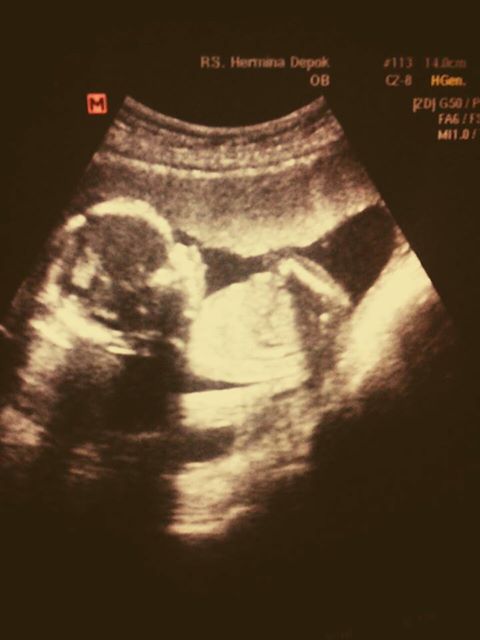

tidak memutuskan untuk langsung pergi ke dokter, suami saya bilang nanti saya

jika usia kandungan sudah memasuki usia 9-10 minggu, karena pada usia tersebut,

ketika di USG sudah telihat detak jantung janin, kalo usia kandungan saat ini

biasanya baru terlihat pelebaran rahim saja. Mmm.. baiklah saya nurut saja apa